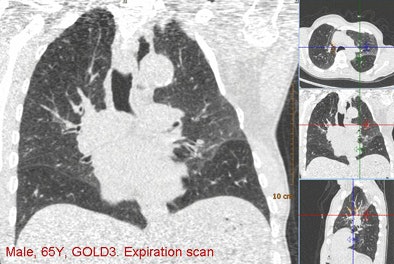

![]() |

| Above, images from the expiration scan of a 65-year-old man with GOLD stage 3. The image shows increased density in some areas, common in expiration scans, but also regions that remain dark and are indicative of air trapping. Below, the overlay images from a single coronal section show that the left upper lobe is normal, while two lobes had emphysema and two had air trapping, indicating mixed-phenotype COPD. |